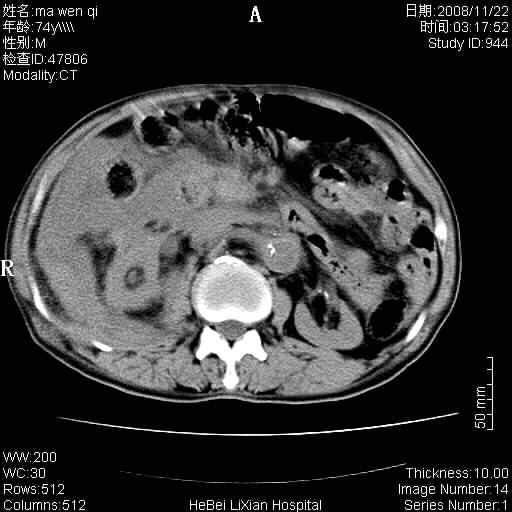

患者男 74岁.突然昏迷,休克6小时.血压70/30,头颅ct未见异常,既往体健.

补充病史,保留导尿10小时,尿袋内只有少许尿液,患者于住院后15小时后去世.

腹主动脉、双侧髂动脉夹层动脉瘤破裂出血进入腹腔。

1)考虑双侧髂动脉瘤并右侧动脉瘤破裂出血,右侧腹膜后及腹腔积血。2)双侧腹股沟疝。

1)考虑,腹主动脉、双侧髂动脉夹层动脉瘤破裂伴右侧腹膜后及腹腔积血。2)双侧腹股沟疝。

1)考虑胸、腹主动脉、双侧髂动脉瘤并右侧动脉瘤破裂出血,右侧腹膜后及腹腔积血。2)双侧腹股沟疝。